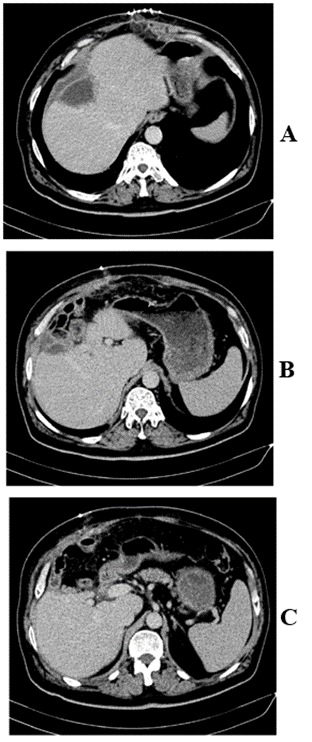

On day two post-operative, patient was transferred to the floor, diet started and well tolerated. Drain was removed on day 8 post-operative and patient discharged home with laboratory follow up and CT- scan (Figure 3) in one month. Ascites stopped on day 15 post-discharge following aldactone administration for one week.

Figure 3: Follow up CT scan in 1 month post-operative showing central hepatectomy.